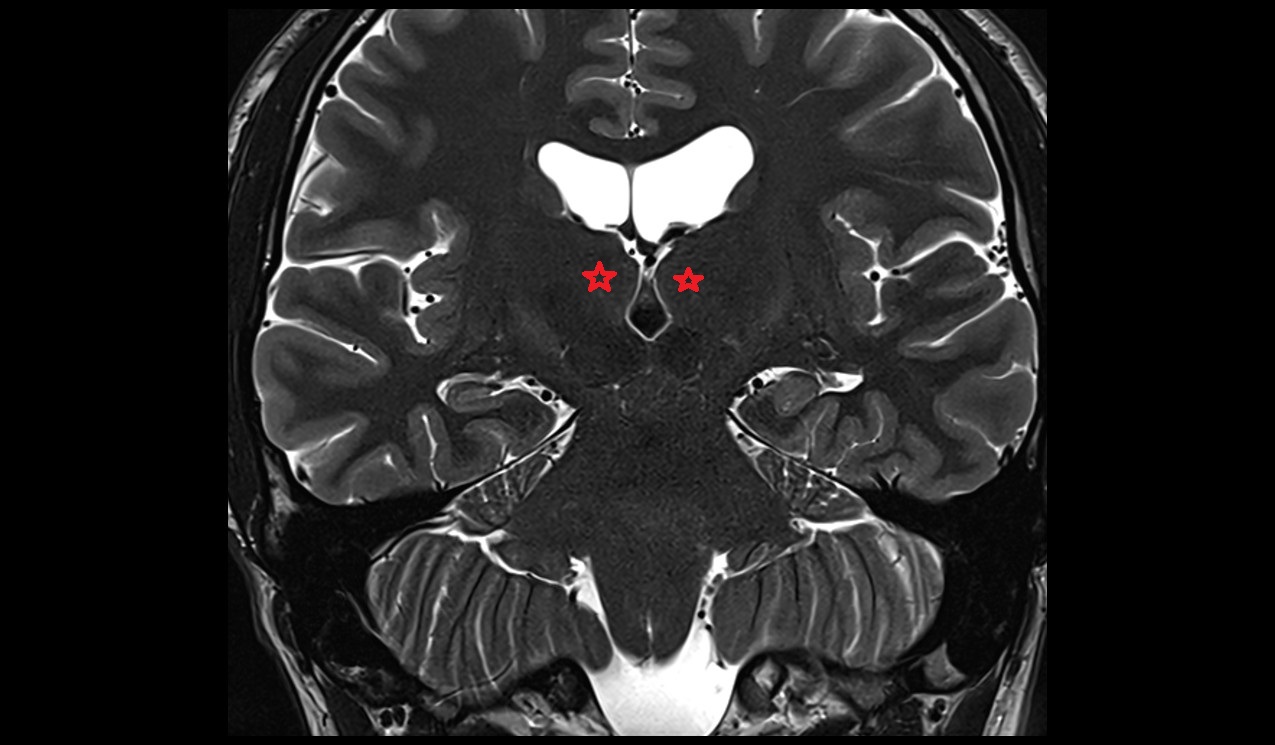

- Dentate nucleus

- Body of hippocampus

- Head of hippocampus

- Tail of hippocampus

- Hippocampus